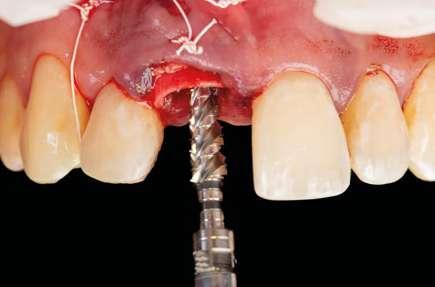

EL PODER DEL WORKFLOW DIGITAL EN IMPLANTOLOGÍA: PRECISIÓN Y CONTROL EN TUS TRATAMIENTOS

La digitalización es una realidad hoy en día en nuestra profesión, por lo tanto, es imprescindible que el odontólogo sepa sacar el máximo partido de todas las tecnologías disponibles con el fin de realizar tratamientos mucho más efectivos y predecibles. En este caso clínico se ha llevado a cabo un tratamiento complicado en una zona de alto valor estético, utilizando un protocolo 100% digital y pudiendo imprimir a nivel local todos los elementos necesarios para hacerlo real.

Introducción

La digitalización es una realidad hoy en día en nuestra profesión, por lo tanto, es imprescindible que el odontólogo sepa sacar el máximo partido de todas las tecnologías disponibles con el fin de realizar tratamientos mucho más efectivos y predecibles. Las soluciones digitales en implantología cubren todas las etapas del tratamiento desde el diagnóstico, la planificación hasta la prótesis definitiva.

Todos sabemos que el aspecto más crítico a la hora de realizar un tratamiento implantológico y de obtener un buen resultado es sin duda la posición 3D de nuestro implante.

Para ello es imprescindible tener bajo control todas aquellas variables que pueden influir en dicha posición tal como la proximidad a dientes vecinos, margen de la futura restauración, volumen de hueso existente, emergencia protética, profundidad del implante, aditamentos protéticos.… Un sinfín de factores a tener en cuenta en los cuales las herramientas digitales van a jugar un papel crucial al permitir, controlar todos esos aspectos antes de abordar el caso, pudiendo verificarlos y cambiarlos, incluso antes de afrontar la cirugía.

La implantología digital nos va a aportar por tanto control y seguridad a la hora de tratar a nuestros pacientes. Por lo tanto, hoy en día es prácticamente impensable que un odontólogo no considere la utilización de todas estas herramientas.

Por otro lado, es imprescindible y fundamental realizar un CBCT de la arcada a tratar para poder visualizar los tejidos duros y hacer una primera valoración del lecho implantario y de la patología existente.

Otra prueba imprescindible hoy en día para nosotros es la realización de un escaneado intraoral que nos aporte la información de los tejidos superficiales y fusionado con el CBCT nos permita valorar los tejidos blandos del paciente.

Para manejar todos estos datos vamos a necesitar de un software de diagnóstico y planificación digital como es el de DTX StudioTM Implant en el cual vamos a abrir tanto el CBCT como el escaneado intraoral y nos va a permitir fusionar ambas mayas utilizando la herramienta SMARTFUSION. En un caso como éste, donde tenemos un incisivo central, superior, derecho, fracturado que vamos a extraer debemos realizar previamente la extracción Virtual en el modelo digital para poder incorporarlo a la planificación de nuestro software.

Con todos estos datos fusionados en el DTX StudioTM Implant, lo que vamos a hacer es utilizar la función SMARTSETUP para tener un encerado Virtual que nos permita determinar la posición de la futura restauración del paciente, en función de la cual colocaremos nuestro implante y el aditamento más adecuado.

En este caso, podemos ver que tenemos un defecto óseo vestibular, se trata de un defecto de una sola pared de la zona a implantar. Intentamos planificar un implante inmediato y observamos la posibilidad de tener un buen anclaje apical por lo tanto nuestra primera opción va a ser la realización de un implante post extracción con regeneración de la pared vestibular mediate xenoinjerto óseo e injerto de tejido conectivo para mejorar el biotipo.

En el caso de obtener suficiente torque, podríamos incluso valorar la opción de cargar dicho implante. En este caso lo que hacemos es planificar también un pilar con el fin de trabajar nuestra prótesis a nivel gingival, siguiendo la filosofía de “One Abutment-One Time (OAOT)”.

Lo realmente extraordinario de este software de diagnóstico y planificación es que en una sola imagen tenemos total control de la posición de nuestro implante y de nuestro pilar, en función del hueso de la encía y de la futura restauración. Por lo tanto vamos a realizar una implantología protética, y biológicamente guiada.

Planificación

Una vez tenemos todos los datos, decidimos como primera opción realizar una cirugía guiada post extracción con regeneración y carga inmediata.

Otra de las ventajas que nos ofrece el software de diagnóstico y planificación DTX StudioTM Implant es la posibilidad de diseñar una férula quirúrgica y exportarla con el fin de poder imprimirla de manera local y acortar así los tiempos de preparación.

A la hora de imprimir nuestra férula localmente, apostamos por utilizar la impresora SprintRay, que de manera muy fácil e intuitiva nos permite imprimir un sinfín de materiales de forma predecible, obteniendo resultados muy precisos y rápidos, es sin duda nuestra impresora de elección por tecnología y materiales.

Aparte de ello, la función TempShellTM nos permite también exportar el diseño de la futura restauración con el fin nuevamente de poder tener un provisional impreso preparado el día de la cirugía. Se trata sin duda de una revolución en cuanto al control de todos nuestros procesos, y en cuanto a eficiencia a la hora de preparar y realizar una cirugía tan compleja.

Cirugía

Con toda nuestra cirugía perfectamente diagnosticada y planificada solo nos queda ejecutarla. 1.- Quitamos la corona ferulizada.

EN IMPLANTOLOGÍA 20 eldentistamoderno mayo/junio 2024

2.- Extraemos de manera meticulosa la raíz del diente afectado.

3.- Legramos toda la zona del lecho implantario con el fin de poder eliminar cualquier resto de tejido de granulación.

4.- Desepitelizamos en margen gingival.

5.- Tunelizamos el defecto vestibular para alojar el injerto de tejido conectivo.

6.- Colocamos injerto de tejido conectivo.

7.- Interponemos membrana reabsorbible entre tejido conectivo y alveolo.

8.- Realizamos osteotomía mediante férula quirúrgica utilizando fresa piloto.

21 eldentistamoderno mayo/junio 2024

9.- Seguimos preparando el lecho utilizando fresado biológico con la OsseoShaperTM

10.- Colocamos implante Nobel Biocare N1TM TiUltra de 3,5x13.

11.- Observamos el torque obtenido de 50N por lo tanto podemos realizar carga inmediata.

12.- Colocamos aditamento N1TM Base XealTM con el fin de trabajar la prótesis a nivel gingivall.

13.- Colocamos pilar provisional.

14.- Rellenamos el gap con creos xenogainTM, compactando para que el hueso llegue lo más apical posible y cubra la superficie implantaria expuesta.

15.- Cortamos pilar provisional y adaptamos el TempShellTM con composite. Podemos comprobar la predictibilidad en cuanto a la posición 3D planificada de nuestro implante.

16.- Colocamos restauración provisional atornillada y fuera de oclusión y traccionamos hacia coronal de los tejidos.

17.- Verificamos nuestro tratamiento con CBCT.

Resultados

Tal vez no sea la primera opción para este tipo de casos con este tipo de defecto, pero debido a las circunstancias personales de nuestro paciente y gracias a nuestro diagnóstico y planificación tan detallados, así como por la ausencia de contratiempos durante el acto quirúrgico, hemos conseguido llevar a cabo un tratamiento bastante complicado en una zona de alto valor estético, utilizando un protocolo 100% digital y pudiendo imprimir a nivel local todos los elementos necesarios para hacerlo real.